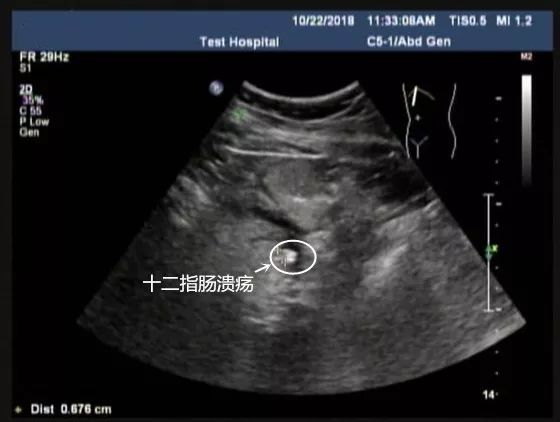

十二指肠球部溃疡: